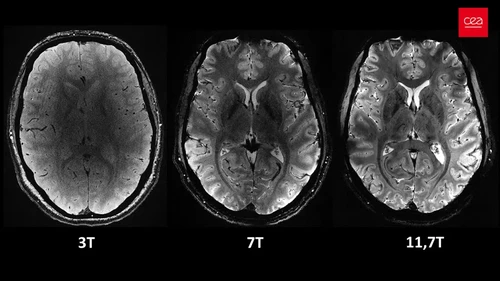

Medan magnet yang diciptakan oleh pemindai adalah sebesar 11,7 tesla, sebuah unit pengukuran yang dinamai menurut penemu Nikola Tesla. Kekuatan ini memungkinkan mesin memindai gambar dengan presisi 10 kali lebih tinggi dibandingkan MRI yang biasa digunakan di rumah sakit, yang kekuatannya biasanya tidak melebihi tiga tesla.

"Dengan mesin ini, kita bisa melihat pembuluh darah kecil yang memberi makan pada korteks serebral, atau detail otak kecil yang selama ini hampir tidak terlihat," ujarnya.